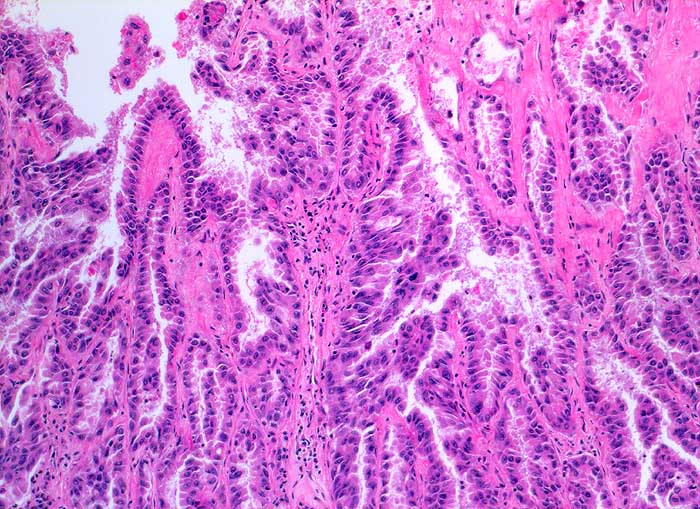

Maligner Pleuraerguss: Adenokarzinom der Lunge

Adenokarzinome der Lunge lassen sich von Adenokarzinomen anderer Primärlokalisation zytologisch nicht unterscheiden. Die Zellen sind meist grösser als Mesothelien und die Kernatypien deutlich ausgeprägt. Falls die Lokalisation des Primärtumors nicht bekannt ist, kann eine immunzytochemische Untersuchung mit TTF1, CK7 und CK20 weiterhelfen. Über 70% der Adenokarzinome der Lunge sind TTF1 positiv. Bei TTF1 Positivität der Tumorzellen sollte ein Schilddrüsenkarzinom ausgeschlossen werden. Unten gezeigt werden zwei verschiedene Fälle.